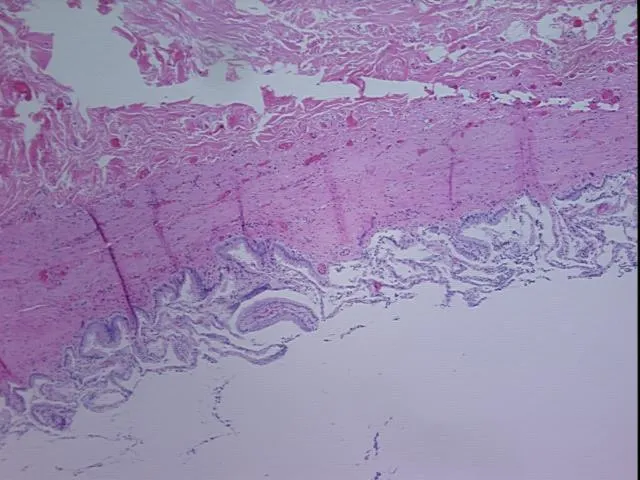

Tissue FFPE Sections, Gallbladder

Description:

Tissue Sections (5x5um), FFPE; Gallbladder; Within normal limitsStability: